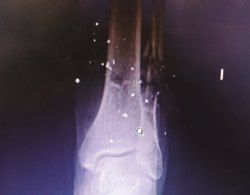

Se trata de un paciente varón de 49 años que presentaba una fractura abierta de peroné de tipo IIIB de Gustilo y Anderson tras sufrir un accidente por arma de fuego. Se observa defecto cutáneo de unos 10 cm en la región posterior de la pierna izquierda (Figuras 1A y 1B). En la radiografía se aprecia una fractura del tercio distal del peroné sin afectar a más estructuras óseas (Figura 2).

Figura 2. Radiografía tomada en urgencias. Se aprecia fractura del tercio distal del peroné con conminución ósea.